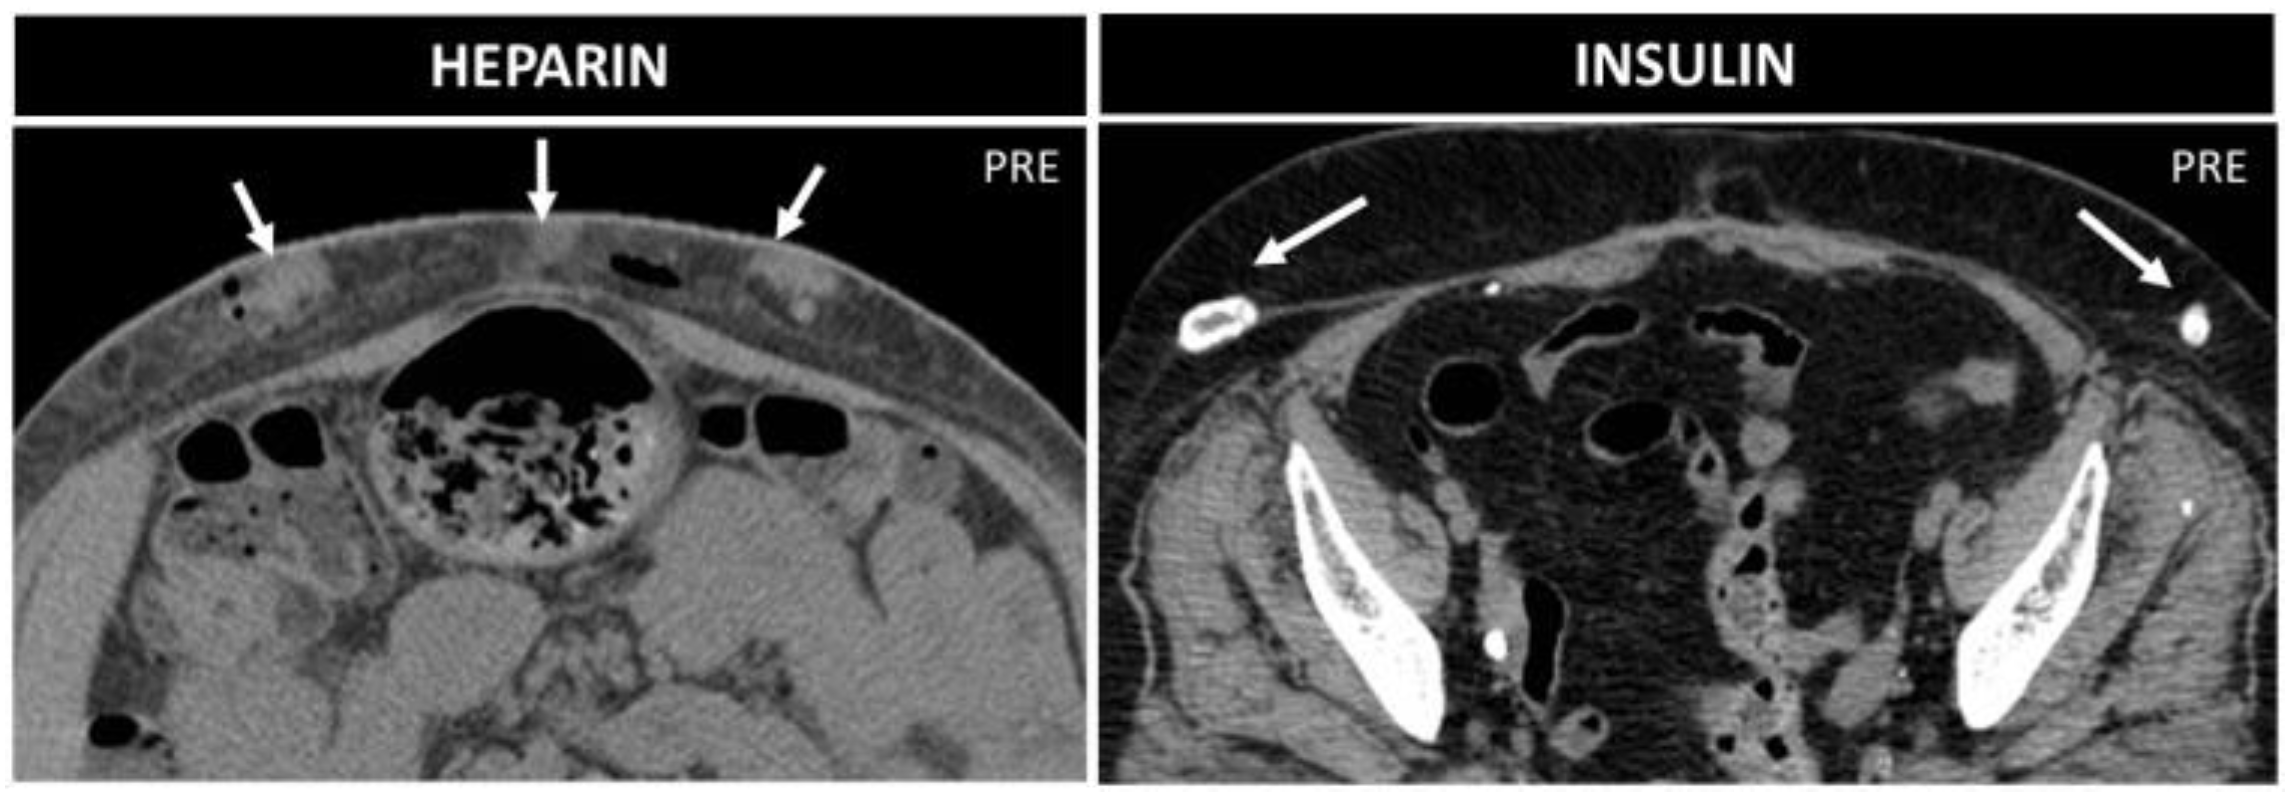

Figure 14. Heparin vs. insulin treatment nodules in two 70-year-old patients. Axial not-enhanced CT in the first patient shows some collections with parenchymatous density, which indicate bleeding, and small air bubbles. In the second patient, instead, lipodystrophies with peripheral calcifications are seen.

Lipohypertrophy is a classical sequela of subcutaneous insulin injections. On CT and MR, it is seen as focal subcutaneous soft-tissue masses, with fat proliferation in a symmetric fashion [41] and calcifications [41,42,43]. “Insulin balls” can also occur, subcutaneous amyloid deposits, visible as soft-tissue masses, with necrotic borders, due to amyloid toxicity [43] (Figure 14).

Management is different between these two conditions: while lipohypertrophy disappears with the suspension of insulin therapy, insulin balls tend to progressively enlarge and require surgical excision [42]. Repeated heparin injections can be associated with air and fluid levels [9]; small soft-tissue nodules, connected to the destruction of the hypodermic fat; and small hematomas with adjacent hazy soft tissue [44] (Figure 14). There is no special management, only a recommendation to alternate the injection spot when performing heparin injection.